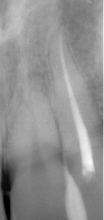

症例4

治療方法 ダイレクトボンディング法

治療期間 1日

治療費用 ダイレクトボンディング 1歯 ¥44,000×4本 ¥176,000(税込)

治療の副作用.リスク 歯を削る必要がある

材質の経年劣化がある

長期的に安定しない

ダイレクトボンディング法

前歯の黒い線が歯のヒビでは?というお悩みで来院されました。矢印部分の黒い線は、歯のヒビではなく詰め物と歯の間の境目に入り込んだ着色が原因です。このケースでは、劣化した詰め物を削ってダイレクトボンディング法で治療を行いました。黒い線の部分と、左側の歯のすき間、中心2本の前歯の詰め物も同時に治しています。